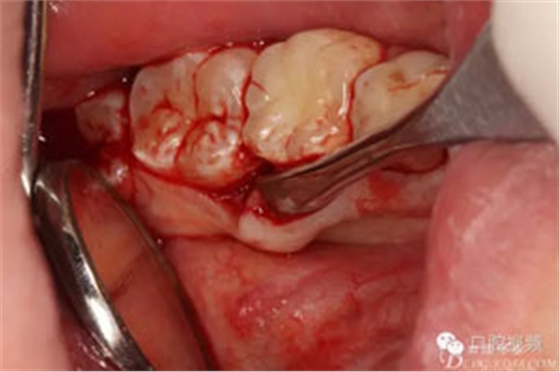

圖6.翻瓣、形成袋形瓣

圖7.通過(guò)CBCT準(zhǔn)確定位,暴露35部分牙冠。